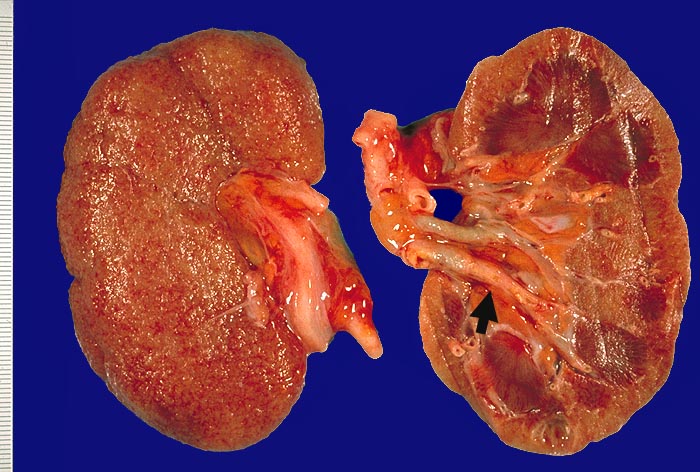

Im allgemeinen ist die Niere infolge von Glomerulumhypertrophie und Tubulushyperplasie vergrössert und derb, die Oberfläche ist granuliert. Bei schwerer Atherosklerose und fortgeschrittener Niereninsuffizienz kann die Niere auch normal gross oder verkleinert sein. Die Kombination von nodulärer Glomerulosklerose, hyalinen Schlingenkappen (=Proteinthromben in den Glomerulumschlingen (> 1916)) oder Kapseltropfen (> 1907) und Arteriolosklerose in Vas afferens und efferens ist beweisend für eine diabetische Nephropathie. Jede einzelne Läsion für sich genommen ist aber unspezifisch. Eine noduläre Glomerulosklerose kann auch vorkommen bei membranoproliferativer Glomerulonephritis (> 2652), Leichtkettenglomerulopathie oder Amyloidose (> 2019). Der nodulären Glomerulosklerose geht bei Diabetikern eine diffuse Glomerulosklerose (> 1906) voraus. Dabei zeigen die glomerulären Basalmembranen und das Mesangium eine progrediente gleichförmige Verbreiterung. Bei der nodulären und diffusen Glomerulosklerose handelt es sich aber wahrscheinlich um zwei pathogenetisch unterschiedliche, sich überlagernde Krankheitsbilder. Typisch bei Diabetikern ist im Unterschied zur arteriellen Hypertonie die Arteriolosklerose von Vas afferens und efferens (> 1911) und oft auch der Vasa recta. Intrarenale Arterien können eine Atherosklerose mit Atheromen zeigen. Subendotheliale Proteinablagerungen teilweise mit Verschluss der Glomerulumschlingen (Schlingenkappen) und knotige Proteinablagerungen in der Bowman'schen Kapselbasalmebran (Kapseltropfen) gehören zu den sogenannten exsudativen Läsionen (> 1919) (> 1920) der diabetischen Nephropathie und führen zu Synechien sowie zur globalen Glomerulosklerose. Gleichzeitig mit den Glomerulumveränderungen treten tubuläre Basalmembranverbreiterungen auf, später eine Tubulusatrophie und interstitielle Fibrose mit Begleitentzündung. Auch die Basalmembranen der peritubulären Kapillaren sind verdickt.

• Verbreiterung des Mesangiums mit Ausbildung von Knoten(noduläre Glomerulosklerose).

• Exsudative Läsionen: Hyaline Schlingenkappen (Proteinthromben in Glomerulumschlingen, im virtuellen Präparat nicht sichtbar) und Kapseltropfen (Proteinablagerungen im Bowman’schen Kapselraum).

• Arteriolosklerose von Vas afferens und efferens (Gefässwandhyalinose durch Ablagerung von Plasmaproteinen und Lipiden in der Gefässwand).

• Intrarenale Atherosklerose.